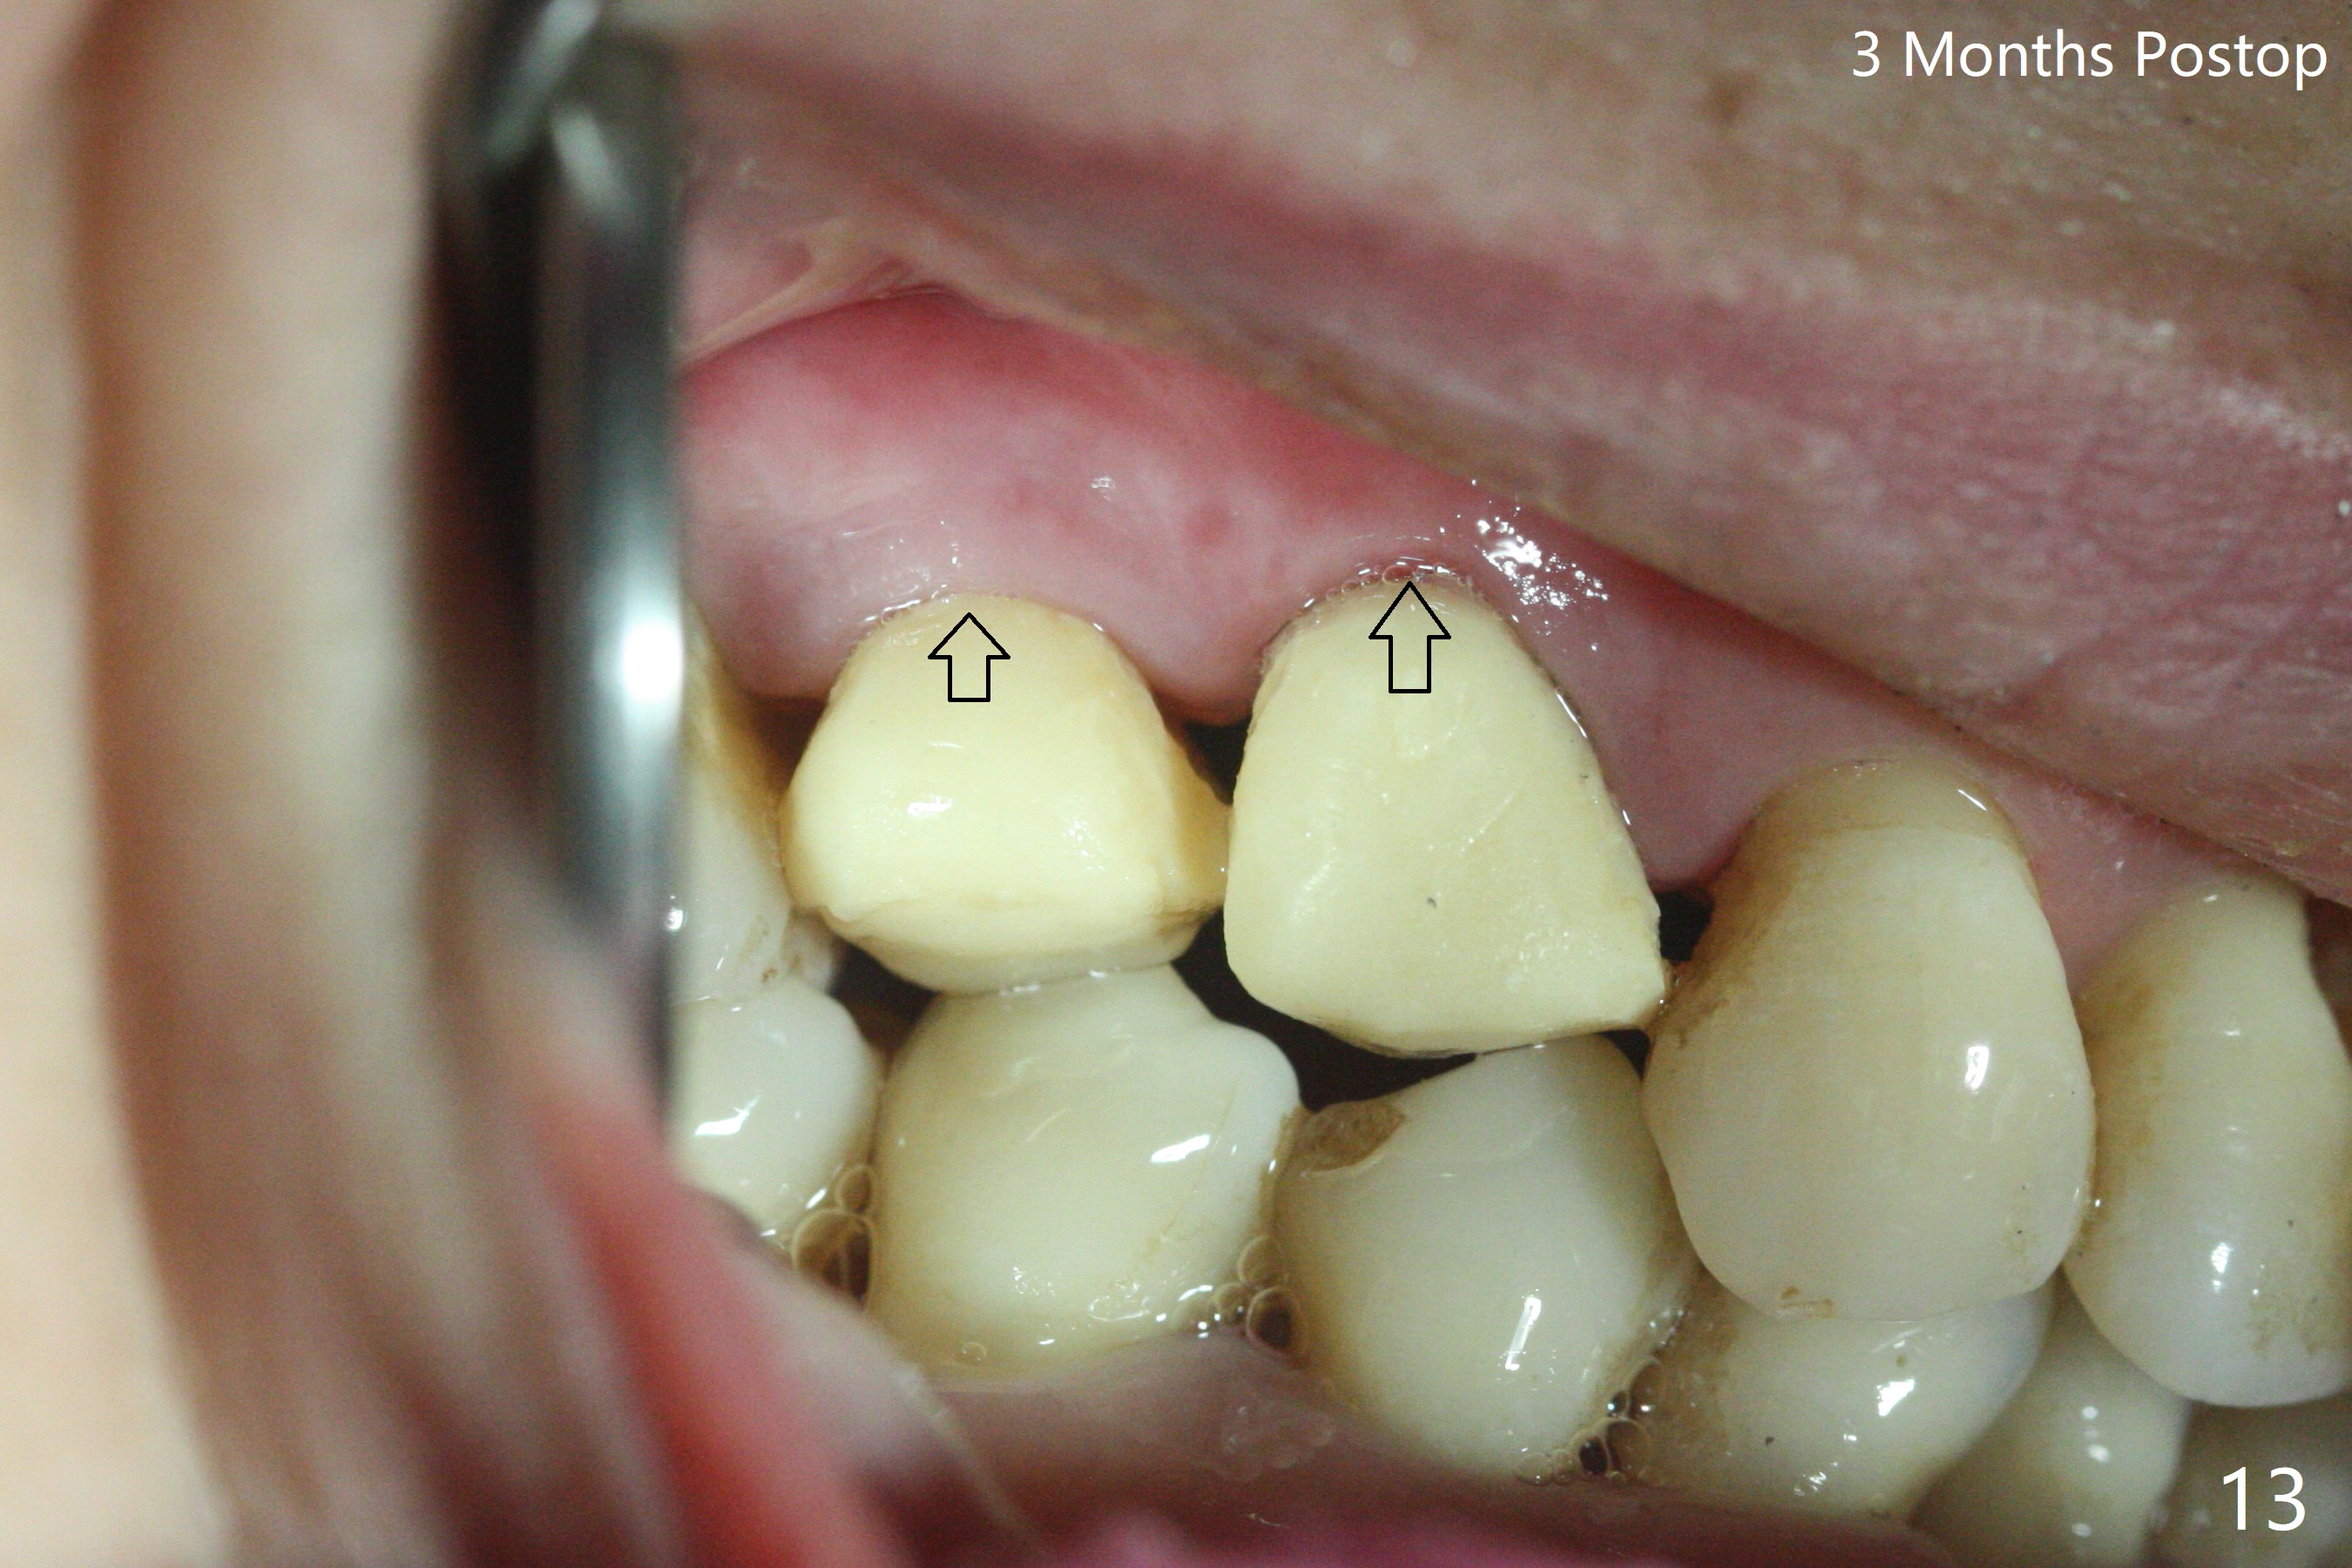

术前CT显示右上4牙槽骨比5窄(图一,二),3.5毫米植体比较合适,况且牙龈厚,基台长的一段式植体显得得当。为了取得最好的植体方位,4先拔除(图三),种植(图四),调整后者深度后,拔除5(术前征求病人同意),开始钻洞(图五),完成种植(图六)。粘性骨粉不仅放置于植体周围,而且6牙根近中(图七),4/5牙槽嵴和龈乳头(P)之间,减少术后龈乳头萎缩(图八:*)。制作两个分开临时牙冠,有利于维持龈乳头。对于病人来说,临时牙冠帮助咀嚼,而对侧拔牙创无法吃饭。术后3个月两个分开临时牙冠(其中一个龈方移位(图九:箭头)保持龈乳头(*)和牙龈外形(图十:*)。临时牙冠取出后,调整基台高度,少量钛屑(不妨大局)附着在健康的牙龈沟(图十一),再次显示两个基台之间龈乳头(图十二:*),衬里,修整的临时牙冠又插回牙龈沟(图十三:箭头),继续维持软组织形态,准备一个月后,调整基台边缘(图十二:箭头),取模。术后五个月大部分骨粉依然保留在植体和邻牙周围,龈乳头退缩不多(图十四: P)。三个月后(术后六个月)钛削无影无踪(图十五,与图十一对比))。永久性牙冠周围空间慢慢会消失(图十六,使用临时性胶水)。